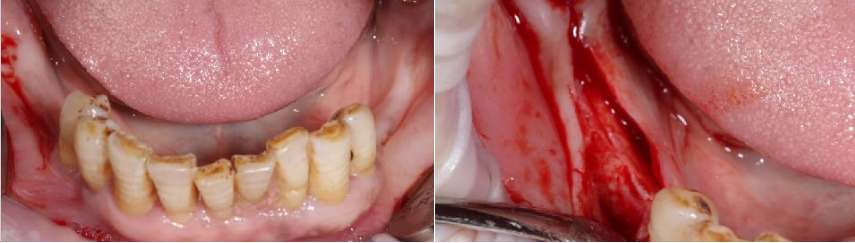

导板引导下种植手术:

上颌植入6颗中科安齿种植体

通过全程数字化导板引导精准植入6颗中科安齿种植体,并且获得非常好的初期稳定性,实现术后即刻修复,患者满意度极佳。